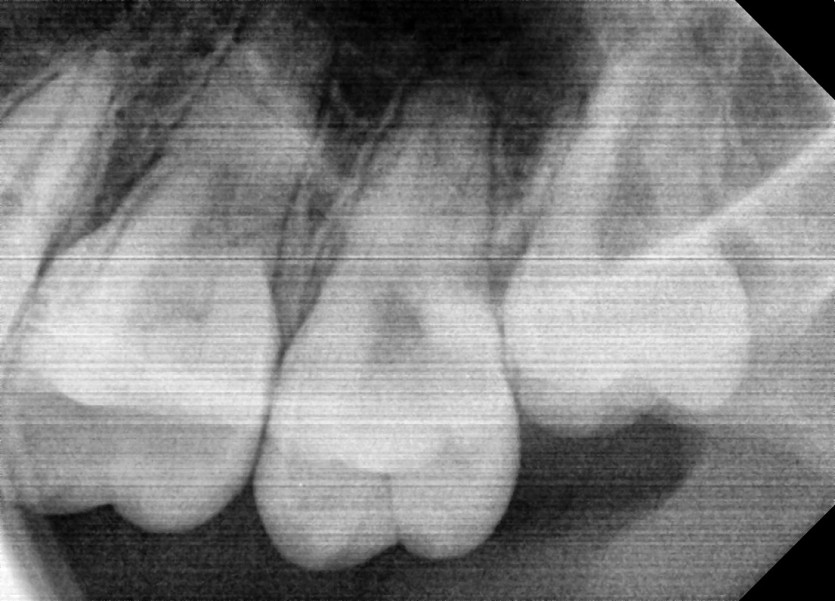

#28 사랑니 발치

구강 외과 전문의가 당일 발치했습니다.